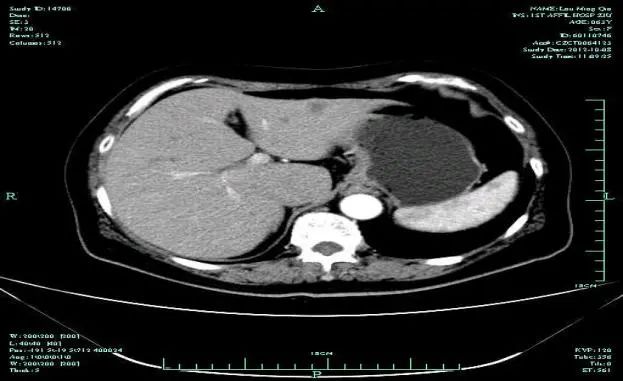

影像学表现:

CT-T

CT-H1

MR-H1

影像学检查结果评估:cPD。